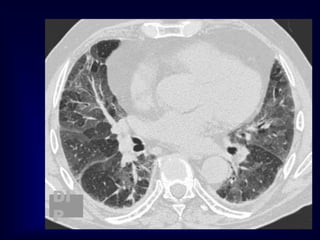

Mosiac pattern

Where is the pathology ???????

in the areas with increased density

meaning there is ground glass

in the areas with decreased density

meaning there is air trapping